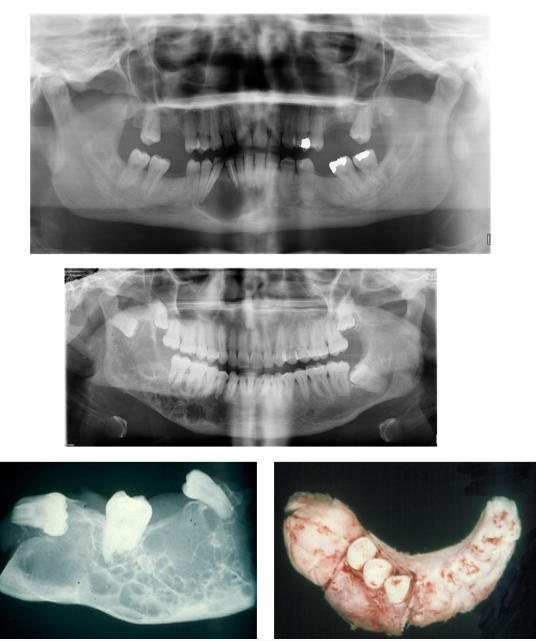

Where do Ameloblastomas commonly affect?

80% are found in the Mandible, most at the angle (but can occur anywhere in jaws)

More aggressive in maxilla

Once it exits bone and enters soft tissues - easier expansile growth - harder to treat

Describe 4 Features of Ameloblastoma?

1) Often Asymptomatic

2) Bucco-Lingual Expansion - degree of facial swelling

3) Root Resorption or Displacement

4) Commonly Multi-locular but can be Uni-locular on Radiographs

How can you differentiate an Odontogenic Keratocyst from an Ameloblastoma?

Amelobastoma have Bucco-Lingual Expansion, whereas an Odontogenic Keratocyst have antero-posterior expansion